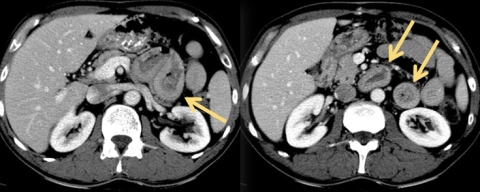

Fig. 2. Lymphome B diffus à grandes cellules du foie, mode de dissémination péri-lymphatique.